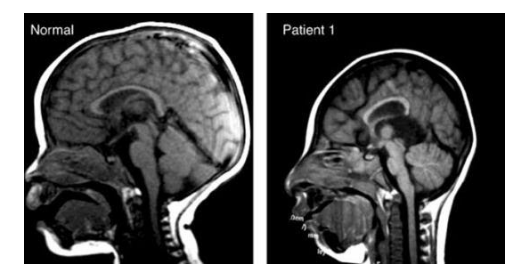

Chẩn đoán tật đầu nhỏ đề cập đến một số em bé có đầu nhỏ khi đo chu vi vòng đầu bằng phương pháp siêu âm trong thai kỳ, hoặc bằng thước quấn quanh đầu sau khi sinh. Nếu chu vi vòng đầu của em bé nhỏ hơn nhiều so với chu vi vòng đầu trung bình của nhóm tuổi hoặc tuần thai thì sẽ được bác sĩ chẩn đoán trẻ mắc dị tật đầu nhỏ.

Thông thường, phép đo sẽ phải có hai độ lệch chuẩn (2SD) dưới mức trung bình, hoặc nhỏ hơn 95% các thai nhi hoặc em bé có cùng độ tuổi thì được coi là tật đầu nhỏ. Siêu âm để xác định tật đầu nhỏ được thực hiện tốt nhất vào tuần thứ 28 hoặc trong 3 tháng cuối thai kỳ.

Các xét nghiệm bổ sung sẽ được bác sĩ chỉ định nếu nghi ngờ thai phụ có bất thường, nghi ngờ thai nhi mắc dị tật đầu nhỏ. Các đặc điểm khác được quan sát trên siêu âm chi tiết giải phẫu thai nhi có thể gợi ý cho một bệnh lý hoặc hội chứng đặc hiệu. Chụp cộng hưởng từ (MRI) có thể cần thiết trong một số tình huống nhất định định để hỗ trợ xác định nguyên nhân gây ra tật đầu nhỏ.

Bệnh đầu nhỏ Microcephaly là dị tật bẩm sinh, trong đó đầu em bé nhỏ hơn nhiều so với bình thường.